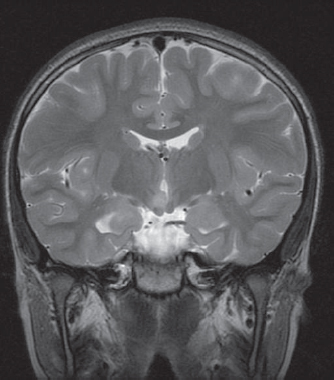

Hypothalamic Hamartoma Neupsy Key Hypothalamic hamartomas (hhs) are rare, heterotopic masses consisting of an abnormal mixture of neuronal and glial cells. they arise from the floor of the third ventricle, tuber cinerium, or mammillary bodies. these developmental malformations can be diagnosed incidentally during routine autopsy. Hypothalamic hamartomas (hh) are rare brain lesions associated with epilepsy and numerous comorbidities. worldwide treatment is varied. there is a paucity of high quality evidence to guide treatment. this study aimed to establish expert consensus on the evaluation and management of hh.

65 Hypothalamic Hamartoma Neupsy Key Hypothalamic hamartomas (hh) are rare, non neoplastic heterotopic tissues which contains normal neurons and glia including oligodendrocytes and fibrillary astrocytes but in an abnormal distribution. Hypothalamic hamartomas (hh) are non neoplastic gray matter lesions, generally occurring within or below the third ventricle. patients most commonly present with gelastic seizures and precocious puberty. Hypothalamic hamartomas (hh) are infrequent, non neoplastic malformations of the hypothalamus with heterogeneous clinical features, with symptoms including gelastic seizures, central precocious puberty, and cognitive or behavioral deficits. A literature search was carried out in electronic databases such as pubmed, cochrane, scopus, sciencedirect, which included the studies reported on “hypothalamic,” “hamartoma,” and.

65 Hypothalamic Hamartoma Neupsy Key Hypothalamic hamartomas (hh) are infrequent, non neoplastic malformations of the hypothalamus with heterogeneous clinical features, with symptoms including gelastic seizures, central precocious puberty, and cognitive or behavioral deficits. A literature search was carried out in electronic databases such as pubmed, cochrane, scopus, sciencedirect, which included the studies reported on “hypothalamic,” “hamartoma,” and. Hypothalamic hamartomas (hh) are infrequent, non neoplastic malformations of the hypothalamus with heterogeneous clinical features, with symptoms including gelastic seizures, central precocious puberty, and cognitive or behavioral deficits. Hypothalamic hamartomas are rare malformations of fetal brain development, affecting development of the hypothalamus, and are placed within the spectrum of grey matter heterotopia. pathologically, lesions show mature neuronal and glial cells and some myelinated fibres. In the present article, we performed a systematic literature search and summarized the information on the reporting patterns related to the pattern of clinical presentation, management, and outcome of hhs. This review is based on the 4th international symposium on hypothalamic hamartomas, which took place september 12 –14, 2019, in washington, dc, and current concepts, experience, and research.